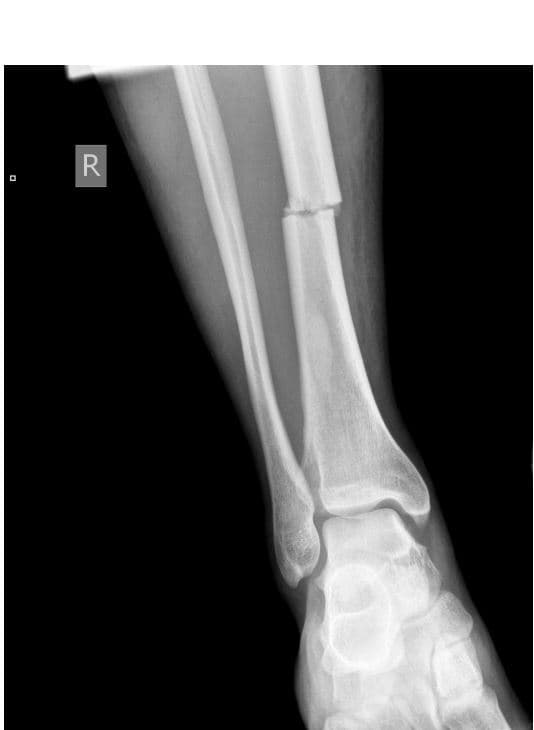

Are these bones axial, appendicular, or both?

How would you describe the fracture?

Name the type of fracture

List ALL of the bones present.

What may have caused this abnormality?